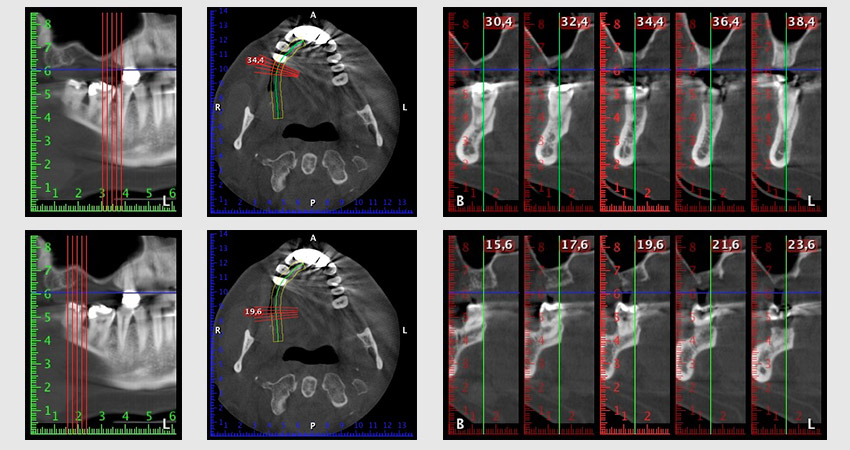

Etwa sechs Monate nach Extraktion der Zähne 16 und 14 wurde zur Planung und Risikominimierung eine digitale Volumentomografie (DVT, Planmeca) erstellt. Hierbei wurde deutlich, dass der Knochen sich nicht in der gewünschten Quantität regeneriert hat (Abb. 2 bis 7).

Abb. 2 bis 7: DVT mit stark reduziertem horizontalen Knochenangebot.